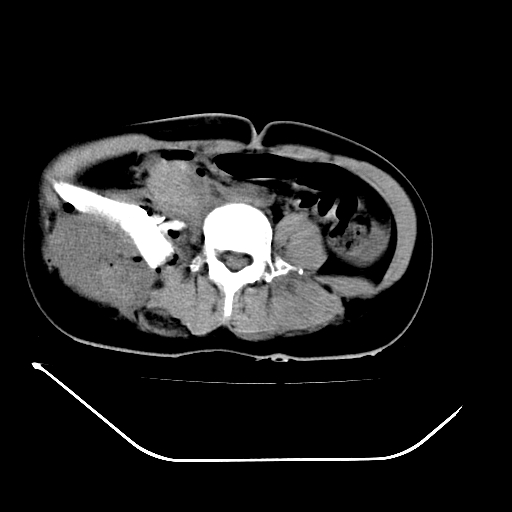

以下是引用liuyue在2008-7-19 13:02:00的发言:[br]1.肝右叶后下段及右肾挫裂伤伴腹腔积血。[br]2.右侧多发性肋骨骨折、横突骨折、右髂骨骨折伴周围软组织挫伤。[br]3.右侧腰大肌肿胀,并可见低密度影,如为气体,则肠道挫裂伤待除外。

以下是引用zhengfaming在2008-7-19 14:42:00的发言:[br]1.肝右叶后下段及右肾挫裂伤伴腹腔积血。脾脏挫裂伤待排[br]2.右侧多发性肋骨骨折、横突骨折、右髂骨骨折伴周围软组织挫伤。[br]3.右侧腰大肌肿胀,并可见低密度影,如为气体,则肠道挫裂伤待除外